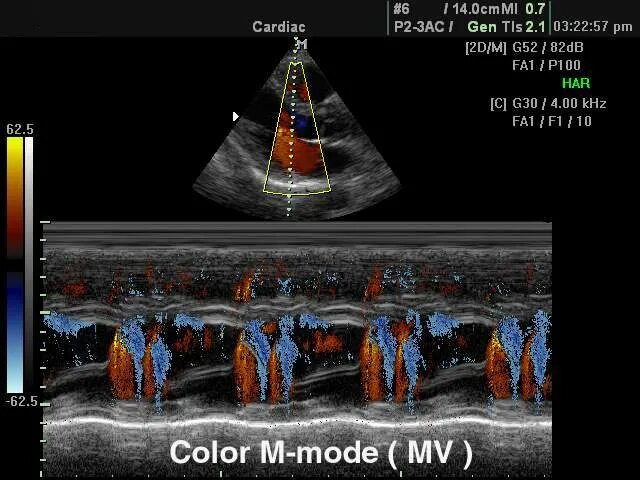

M mode